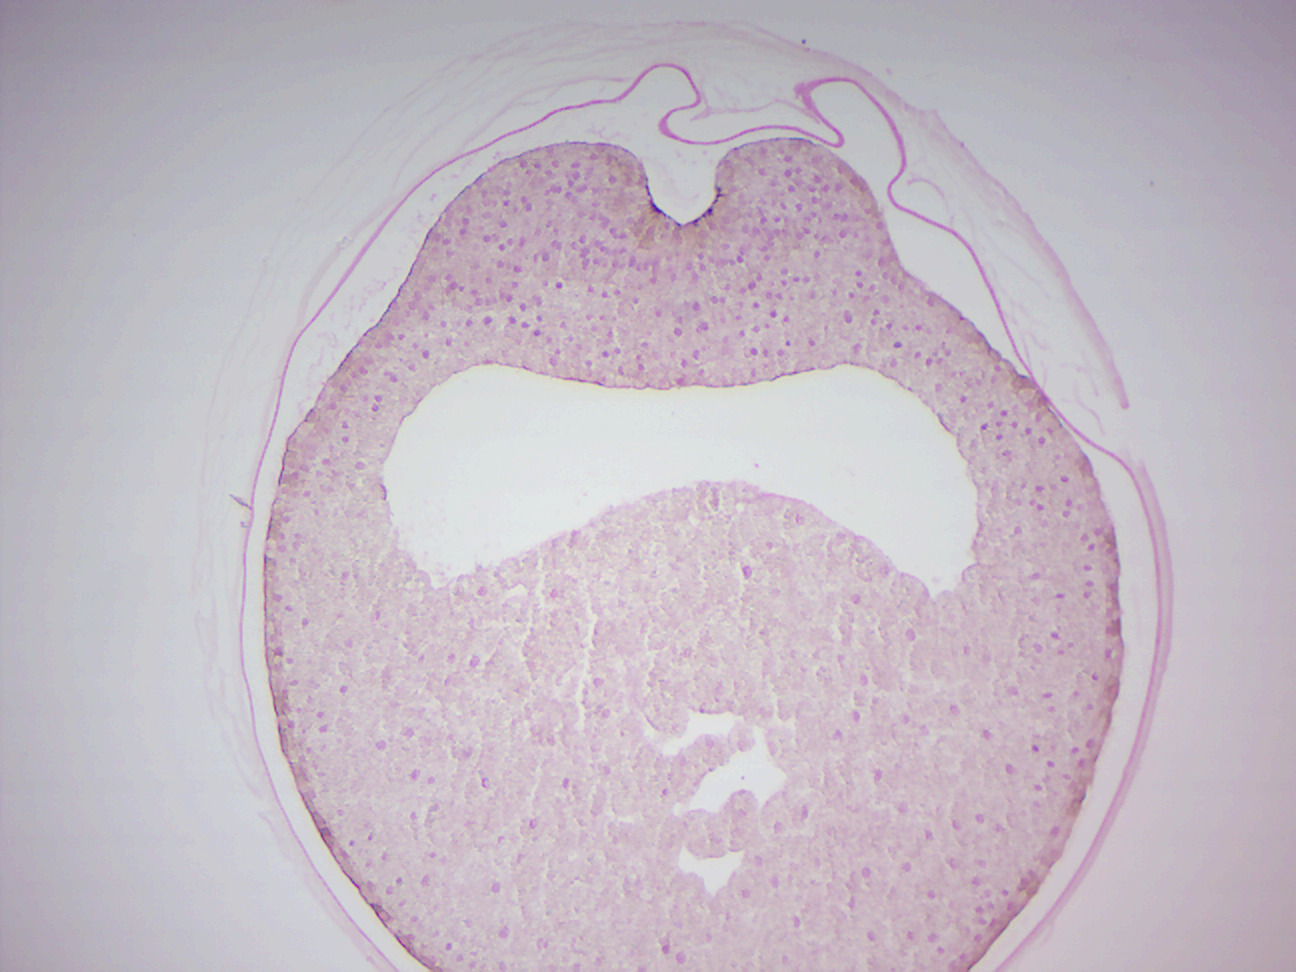

What Is A Neural Groove In Biology . The head and trunk regions both undergo variants of primary neurulation, and this process can be divided into four distinct but spatially and temporally overlapping stages: The neural folds converge and convert the neural groove into the neural tube. A neural groove forms, visible as a line along the dorsal surface of the embryo. The central area of the neural plate invaginates and becomes the neural groove. The early central nervous system begins as a simple neural plate that folds to form a neural groove and then neural tube. As the folds fuse, the neural tube. The neural groove is a midsagittal groove that appears in the neural plate during embryonic development, where the sides elevate to form the. A midsagittal groove called the neural groove appears in the plate, and the sides elevate to form the neural folds. This early neural is initially open initially at each end forming the neuropores. This whole complex of neural folds and the groove is called the neural plate.

The central area of the neural plate invaginates and becomes the neural groove. The neural groove is a midsagittal groove that appears in the neural plate during embryonic development, where the sides elevate to form the. The head and trunk regions both undergo variants of primary neurulation, and this process can be divided into four distinct but spatially and temporally overlapping stages: A neural groove forms, visible as a line along the dorsal surface of the embryo. This whole complex of neural folds and the groove is called the neural plate. A midsagittal groove called the neural groove appears in the plate, and the sides elevate to form the neural folds. As the folds fuse, the neural tube. The early central nervous system begins as a simple neural plate that folds to form a neural groove and then neural tube. This early neural is initially open initially at each end forming the neuropores. The neural folds converge and convert the neural groove into the neural tube.